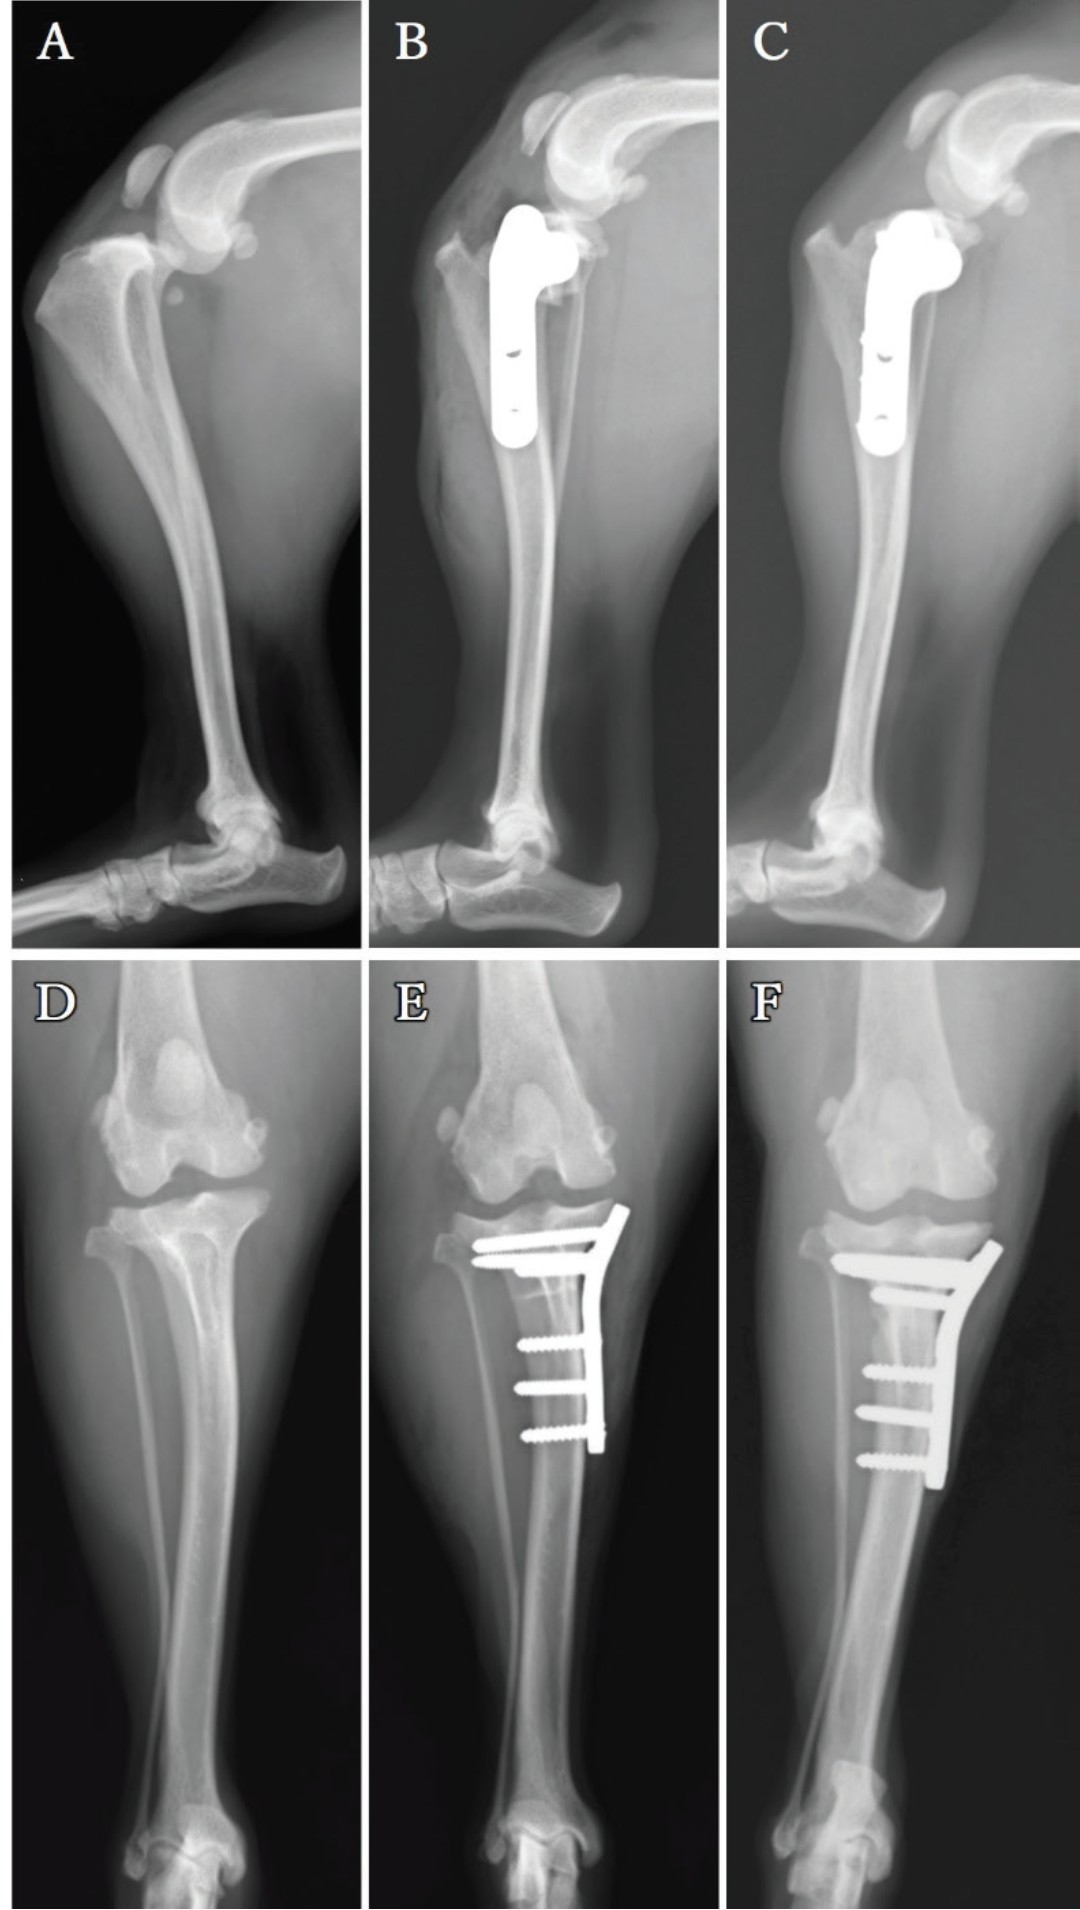

右后肢术后8周,左后肢出现负重跛行,左膝关节过度伸展时疼痛和肿胀,前抽屉试验和胫骨压缩试验结果为阳性。X光显示左膝关节存在髌下脂肪垫征象和胫骨向前移位,未见明显的肢体畸形(图4A和D)。

图4. 左后肢的侧位X光片(A-C)和后前位X光片(D-F)。术前左膝关节的髌下脂肪垫征象和胫骨向前移位(A)。未见明显的肢体畸形(D)。2.4毫米TPLO钢板放置后的术后X光片(B和E)。术后13周,胫骨和骨片完全愈合(C)。13周的后前位X光片(F)。随访显示植入物无脱位迹象。

术前X光片显示TPA为25°。选择了一个2.4毫米的TPLO钢板用于TPLO。与右后肢的测量结果相同,左后肢的D1和D2分别为7.5毫米和8.2毫米。

术后13周,左后肢的截骨线已不可见,两侧肢体均无残留不适或跛行。由于骨愈合,截骨线不明显(图4C)。植入物对齐且骨骼保持稳定(图4F)。